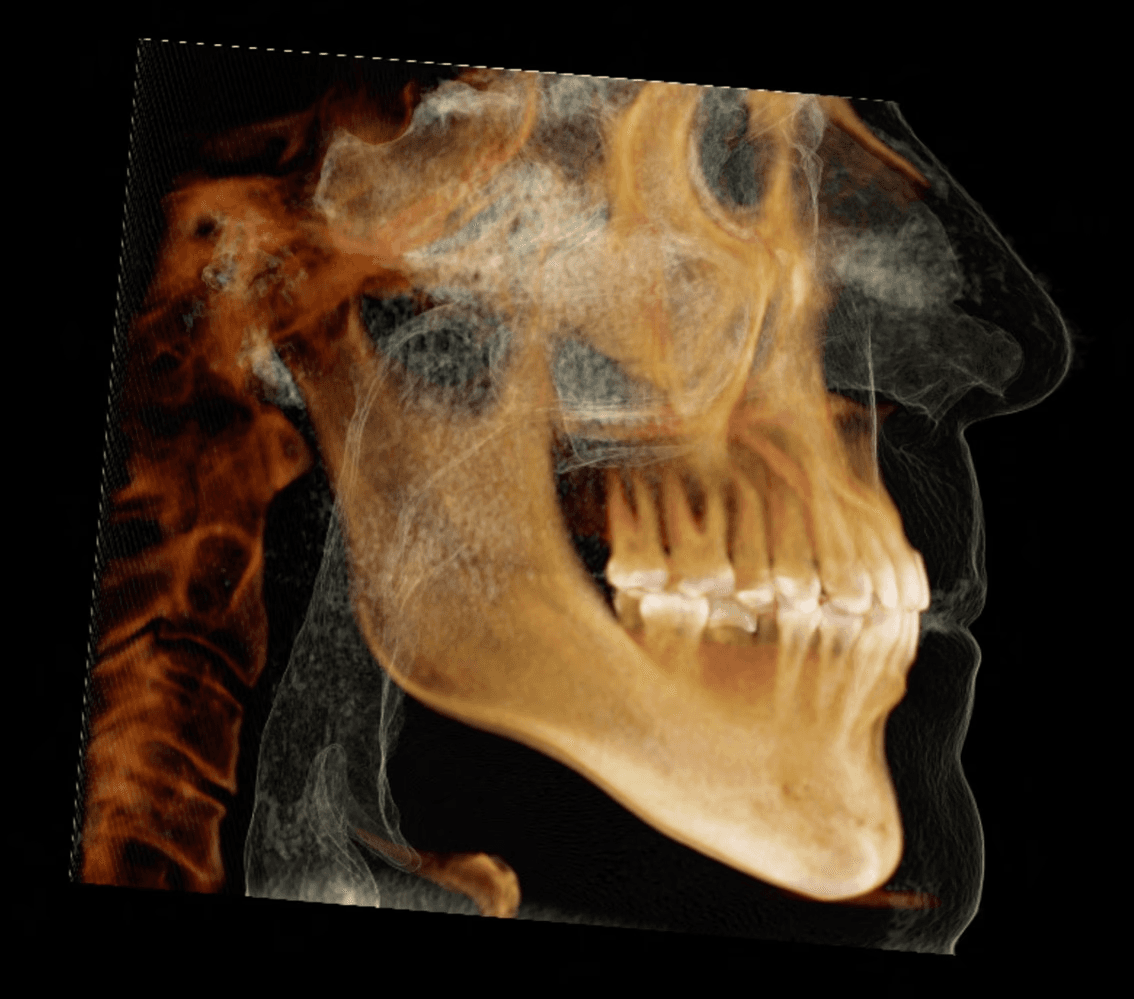

Initial treatment

X-RAYS